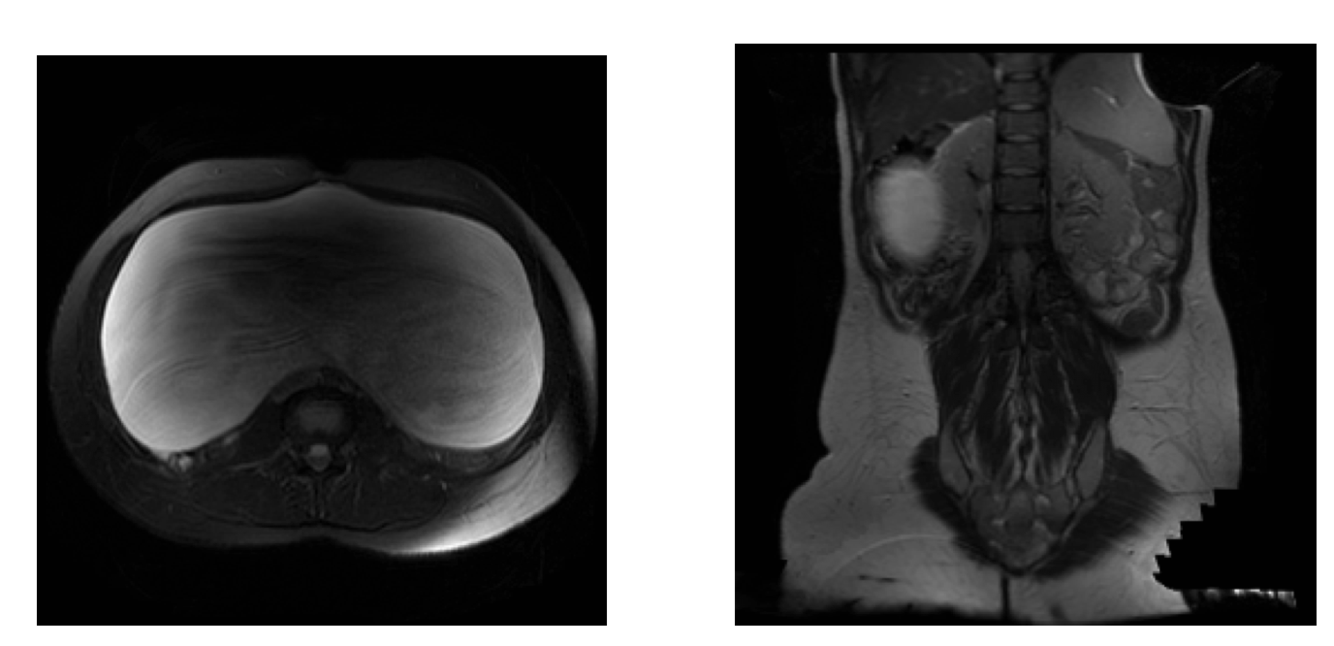

Identify

What this be?

Serous cystadenoma